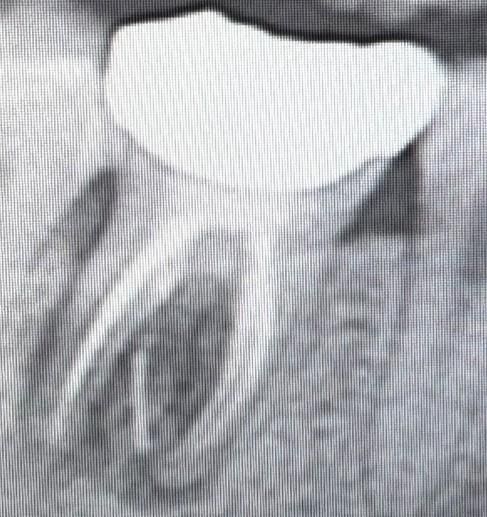

엑스레이 사진입니다.

병원에서는 엑스레이만 찍었고, 엑스레이 사진을 보시곤 치아 아래 흰색 줄(?) 부분이 뿌리가 부러진 것이니 발치를 해야한다고 했습니다.

그런데 집에 와서 좀 찾아보니 신경치료기구가 파절된 것이거나, 신경관 충전재 등이 빠져나온 것일 확률도 높다고 하더라구요.

1. 치아 뿌리 사이에 있는 흰색 줄 같이 생긴 부분이 뿌리가 부러진건가요?

기구파절의 양상으로 보이긴하는데 그게 신경치료 실패의 원인은 아닐겁니다 어쨌든 염증이 생긴 상태이기 때문에 처치를 해주어야 더 잇몸뼈가 안 녹습니다 재신경치료, 치근단절제술 시도해볼 수 있고 안되면 빼야합니다